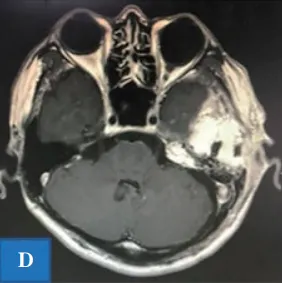

图1D:术后磁共振成像。